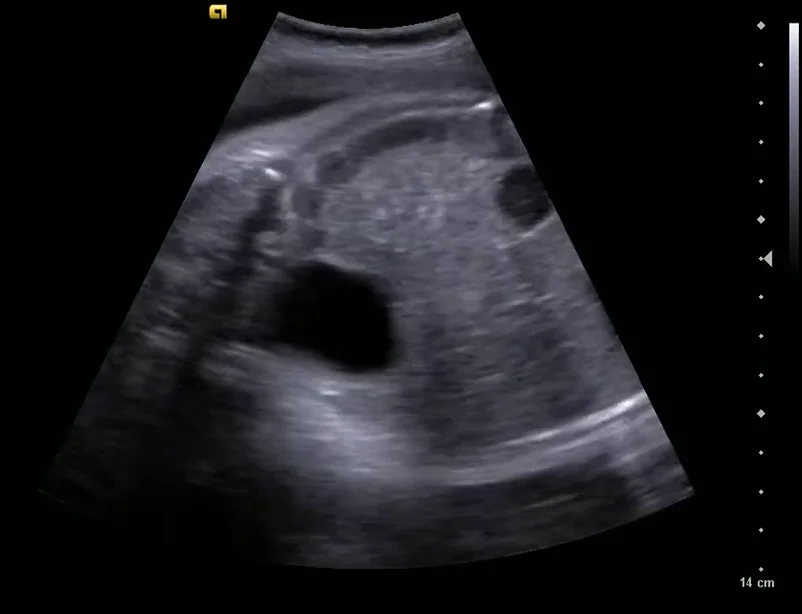

• Các biến thể phát triển của thận

• Bất sản thận một bên (Unilateral Renal Agenesis)

• Thận lạc chỗ vùng chậu thai nhi (Pelvic Kidney)

• Thận móng ngựa thai nhi (Horseshoe Kidney)

• Thận lạc chỗ bắt chéo dính nhau ở thai (Crossed fused renal ectopia)

• Nang nước tiểu / Tràn dịch quanh thận ở thai (Urinoma)

• Thận loạn sản đa nang thai nhi (Multicystic Dysplastic Kidney - MCDK)